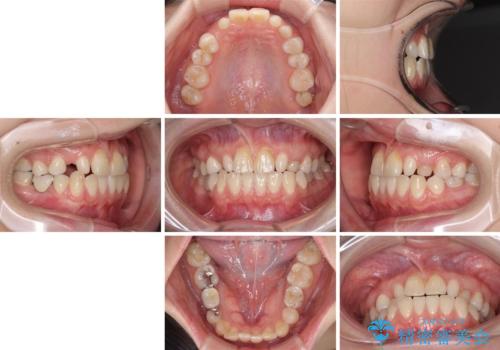

欠損と残存乳歯 矯正治療とインプラント治療

- 残存した乳歯や歯の欠損、歯並びを気にして来院された患者様です。

乳歯を残した状態は予後がよくないこと、矯正治療と補綴治療を総合的に進めていきたいとのことで、インビザラインによる矯正治療とインプラント補綴治療を並行して進めていくこととしました。

当院は矯正治療もインプラント補綴治療も、同一の歯科医師が担当するため、矯正治療を行いながら、最適なタイミングでインプラント補綴治療を行うことが可能です。

気になっていた部分がすべて解消され、患者様には大変満足していただきました。